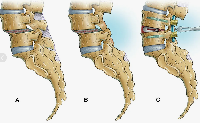

В случае перелома шейки бедра компания МосРентген Центр госпитализирует в Склиф для эндопротезирования.